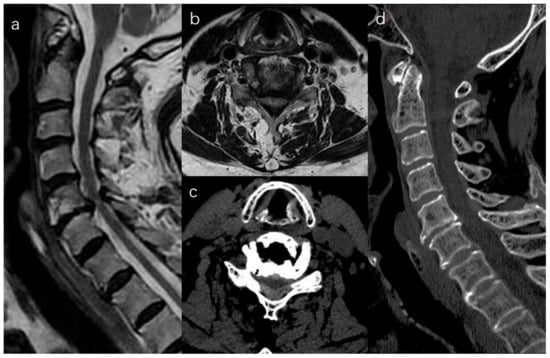

:1. Introduction

2.2. Surgical Procedure

2.2.2. Unilateral Biportal Approach for Bilateral Laminectomy (Video S1)